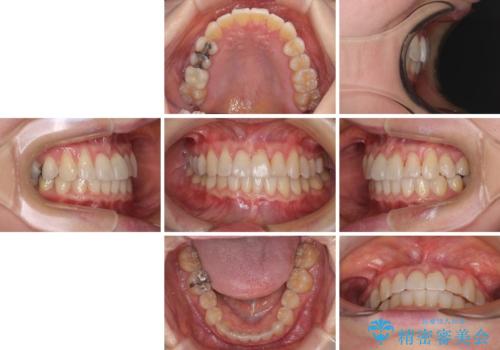

前歯のクロスバイト インビザライン矯正で改善

- 1年8ヶ月

- 治療回数

- むし歯治療を契機に、長年気にしていた前歯のクロスバイトの改善を希望された患者様です。

汚れが溜まりやすく、歯ぎしりがうまくできないため、インビザラインを用いて矯正治療を行うこととしました。

インビザラインによる前歯のクロスバイトの改善は、治療期間中に前歯でしか咬めない時期が続いたり、歯肉退縮や歯髄壊死のリスクが高まったりと、治療中にトラブルを抱えることがあります。

特に上顎側切歯(真ん中から2番目の歯)が舌側に引っ込んでいるケースは、インビザラインでは改善しきれないことがあると言われています。